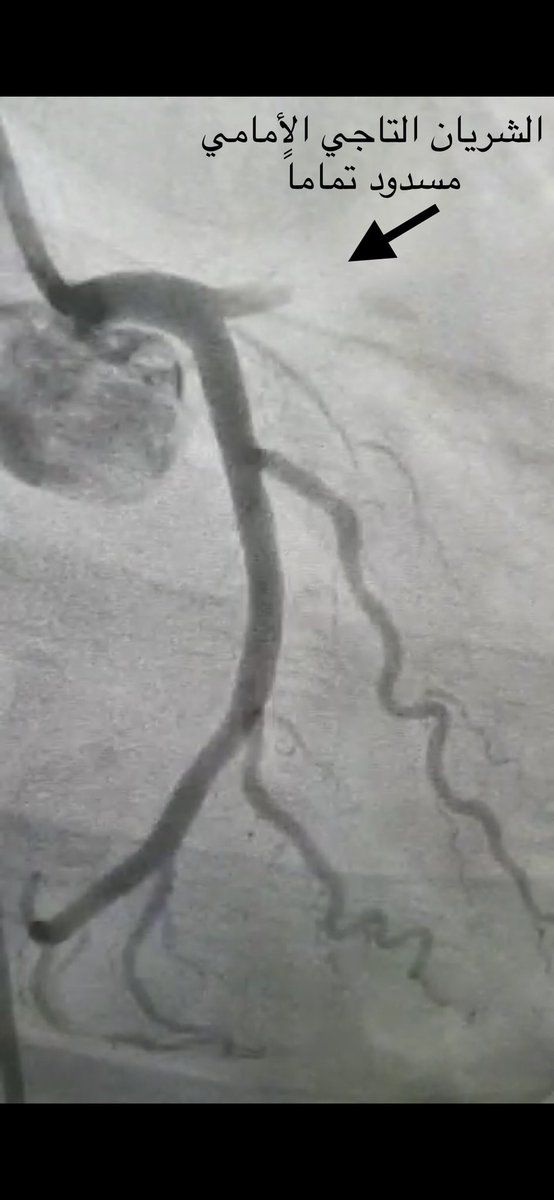

بينت القسطرة انسداد كامل بالشريان التاجي الأمامي

وتم علاجها بنجاح